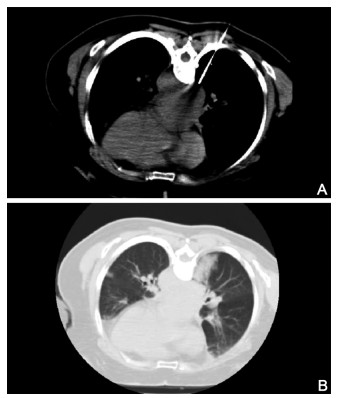

Analysis of the main influencing factors of bleeding and pneumothorax complication under CT-guided lung biopsy

ZHANG Guang-dong, YUAN Mei, LI Wu-hao, MEI Qi, TAN Yu-lin

2021, 19(5): 771-774. doi: 10.16766/j.cnki.issn.1674-4152.001913

Objective  To explore the safety of CT-guided lung biopsy, analyze the high risk factors of bleeding and pneumothorax, and summarize the operational skills to reduce the incidence of bleeding and pneumothorax.  Methods  The clinical data of 285 patients with lung mass who underwent CT-guided lung biopsy in the first affiliated Hospital of Bengbu Medical College from September 2018 to April 2020 were analyzed retrospectively. The risk factors such as sex, age, tumor size, distance from pleura, puncture angle, puncture depth, puncture times, basic lung disease, lesion location, patient position and other related factors were divided into different grades. Chi-square test was used to analyze whether there were differences in the incidence of bleeding and pneumothorax among statistical data, and logistic regression was used to analyze the independent risk factors of bleeding and pneumothorax.  Results  CT-guided lung biopsy and puncture: a report of 285 cases, 52 (52/285, 18.25%) had bleeding and 43 (43/285, 15.09%) had pneumothorax. Univariate analysis showed that postoperative bleeding is related to the distance between the mass and the pleura and the depth of puncture needle (all P < 0.05). The occurrence of pneumothorax after surgery was related to factors such as the distance between the lesion and the pleura, the depth of puncture, the number of punctures, and basic lung disease (all P < 0.05). Logistic regression analysis analyzed that the puncture distance was an independent risk factor for bleeding; the basic lung disease, the number of punctures and the puncture distance were independent risk factors for pneumothorax.  Conclusion  CT-guided lung biopsy is safe and has fewer serious complications. Basic lung diseases, long puncture distance and more puncture times are the main risk factors of bleeding and pneumothorax in CT-guided lung biopsy. Reducing the number of punctures, avoiding pulmonary vesicles and cavities, and choosing a relatively short puncture path can effectively reduce the postoperative complications of lung biopsy.